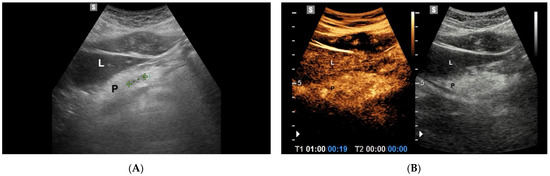

4.1. Mucinous Cystic Neoplasms

4.1.1. IPMN

4.1.2. MCNs

4.2. Serous Cystic Neoplasms